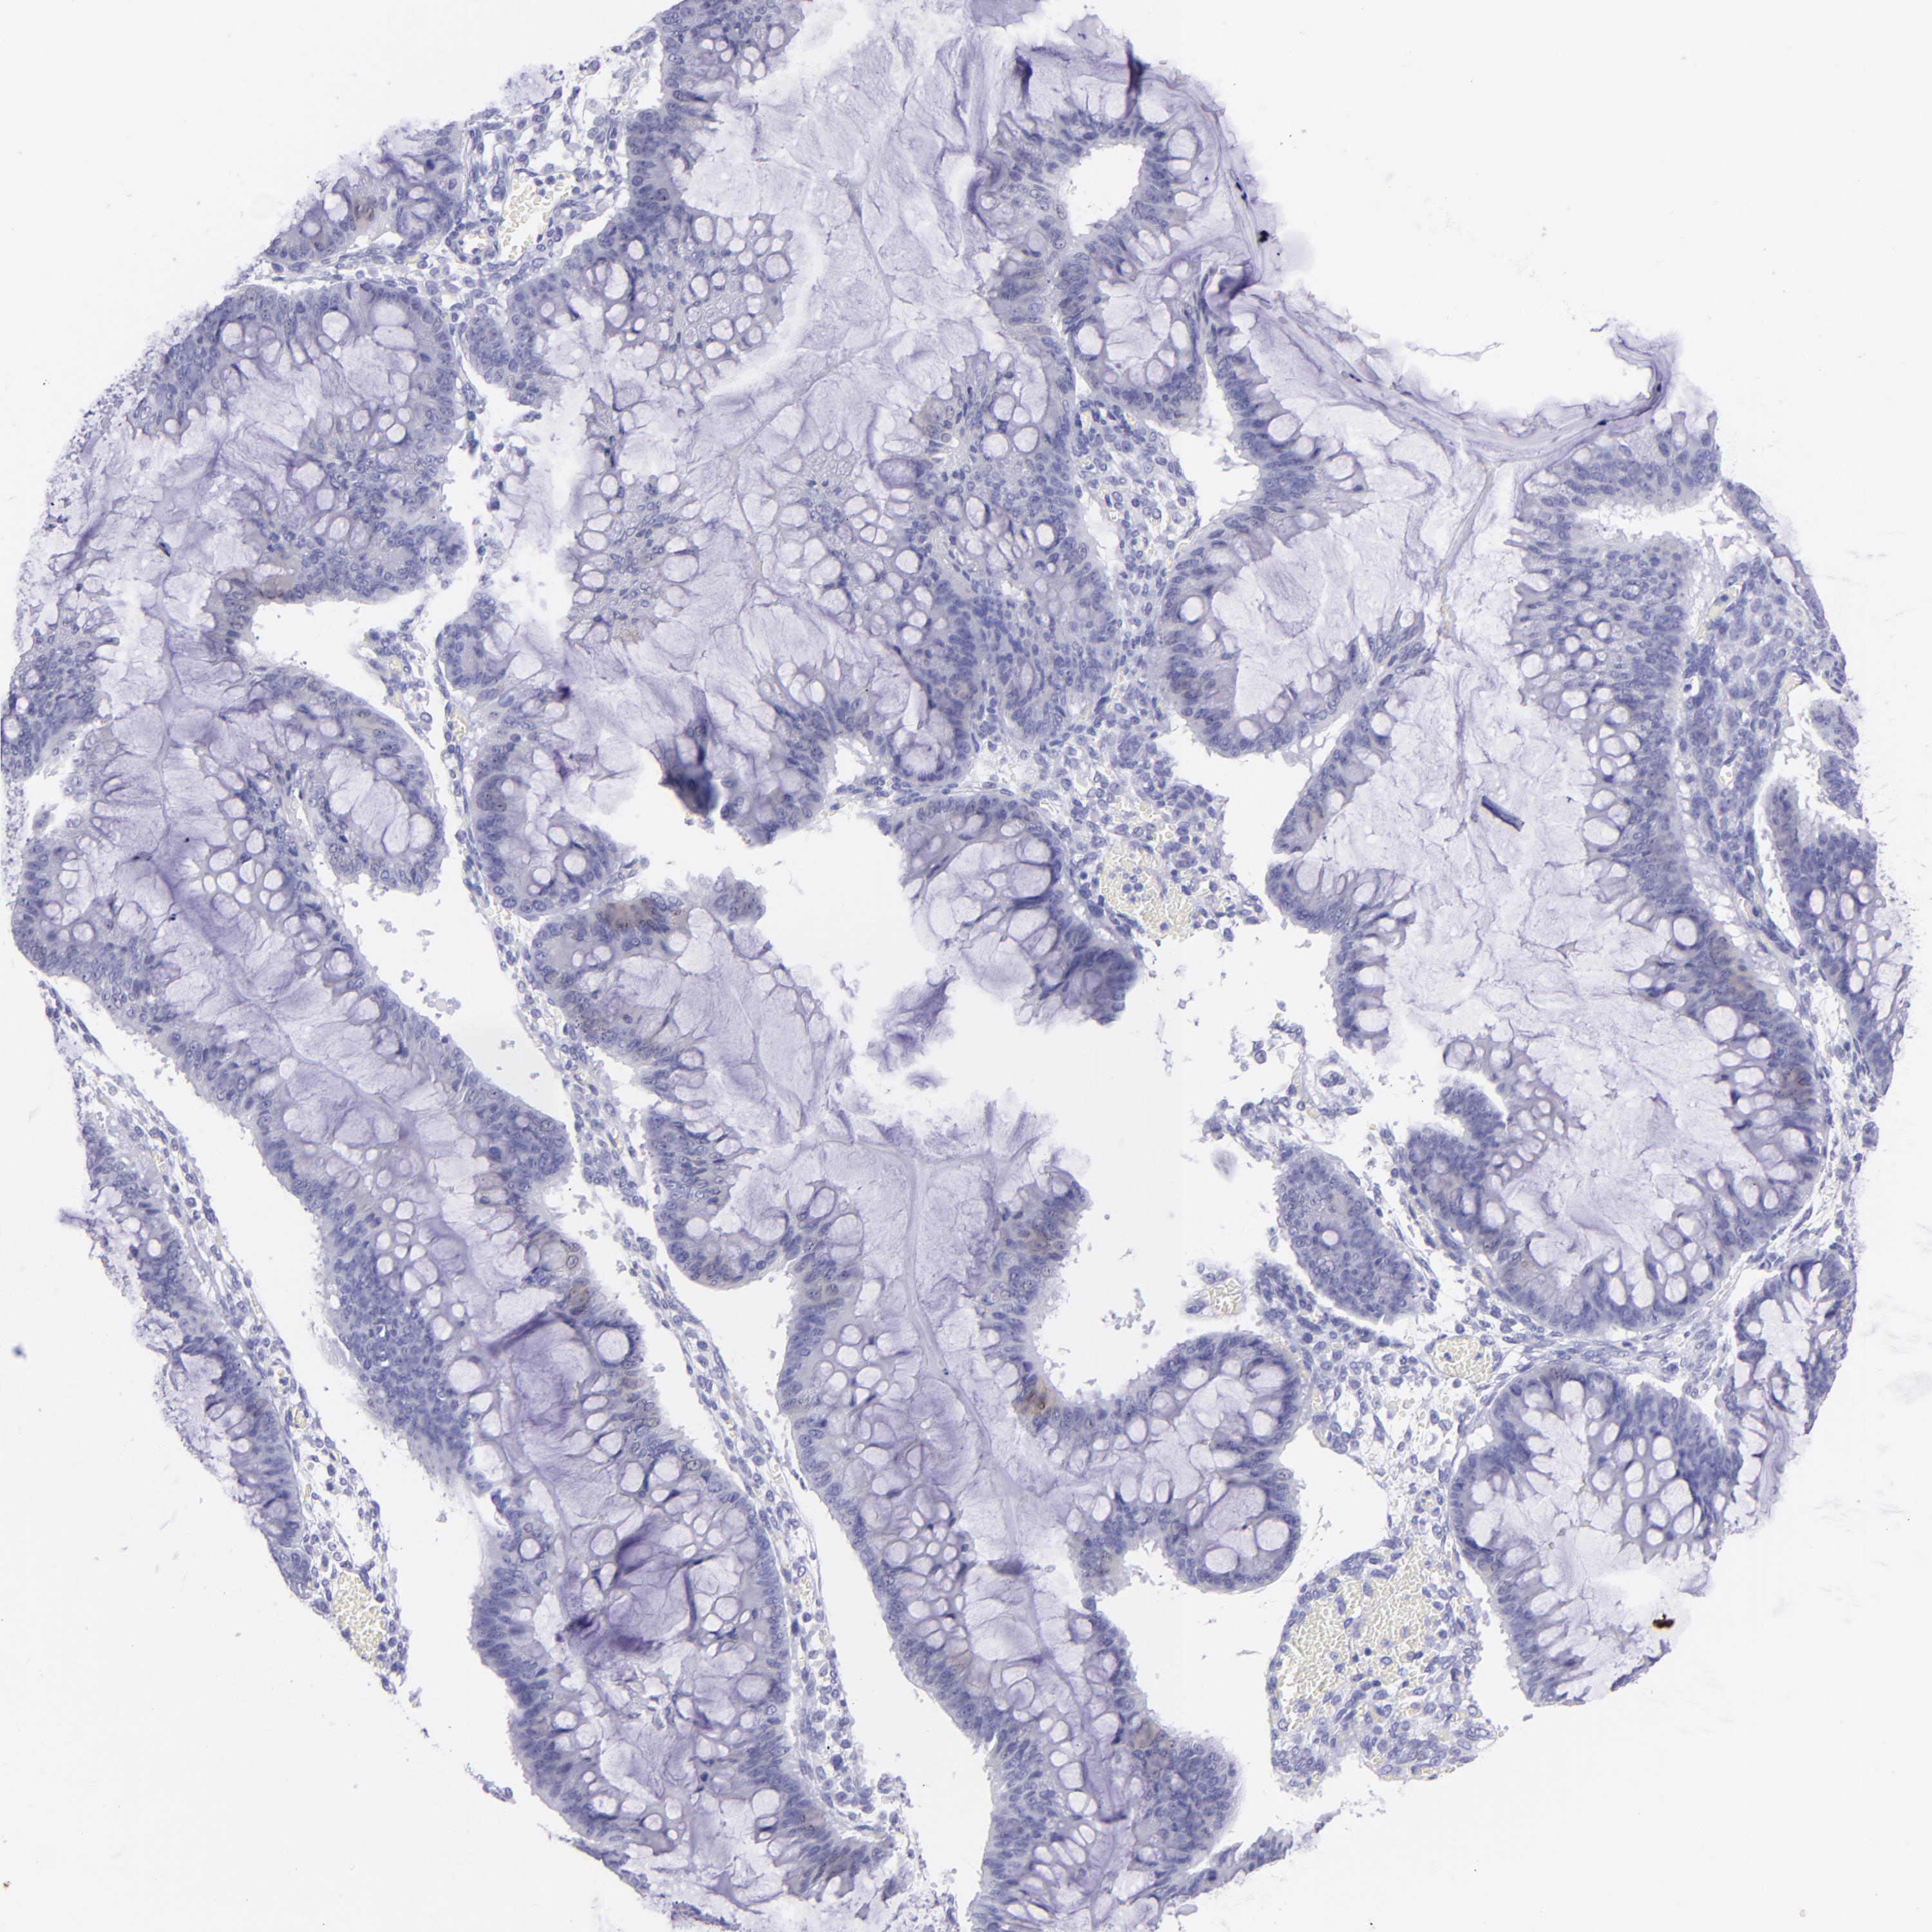

OVARIAN CANCER - Protein expressioni

A mouse-over function shows sample information and annotation data. Click on an image to view it in a full screen mode. Samples can be filtered based on level of antibody staining by selecting one or several of the following categories: high, medium, low and not detected. The assay and annotation is described here.

Note that samples used for immunohistochemistry by the Human Protein Atlas do not correspond to samples in the TCGA dataset.

Antibody stainingi

Antibody staining in the annotated cell types in the current human tissue is reported as not detected, low, medium, or high, based on conventional immunohistochemistry profiling in selected tissues. This score is based on the combination of the staining intensity and fraction of stained cells.

Each image is clickable and will lead to virtual microscopy that enables deeper exploration of all samples and also displays staining intensity scores, fraction scores and subcellular localization as well as patient and tissue information for each sample.

Antibody HPA009177

Antibody CAB002661

Cystadenocarcinoma, serous, NOS

Carcinoma, endometroid

Cystadenocarcinoma, mucinous, NOS

Carcinoma, NOS